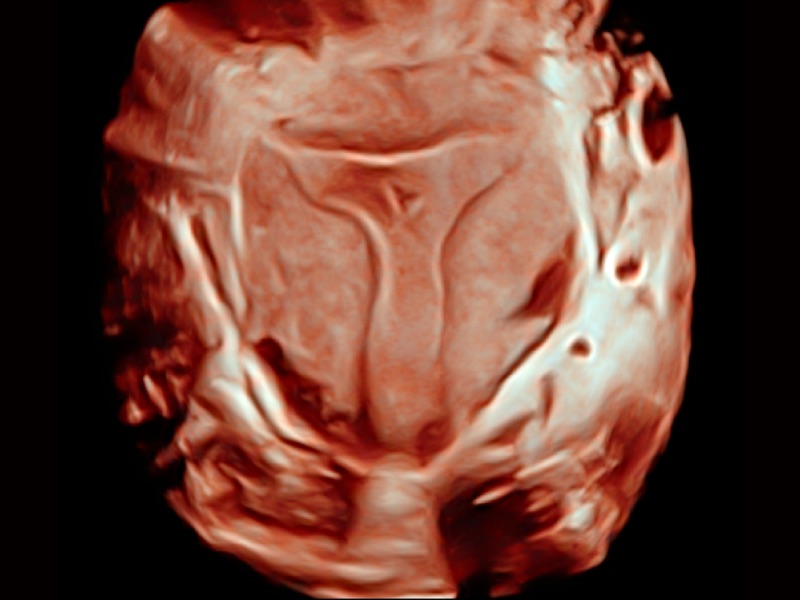

心血管应用

支持运动和药物负荷协议、多心动周期存储选择,为临床观察心肌负荷状态下的室壁节段运动、评估心肌缺血状态提供更多的解决方案。

通过心肌识别技术和二维斑点追踪技术相结合,计算心肌各节段的应变应变率、速度、位移并以曲线图显示,实现整体或者局部心肌定量分析。同时可呈现牛眼图直观和准确诊断心肌的运动情况。